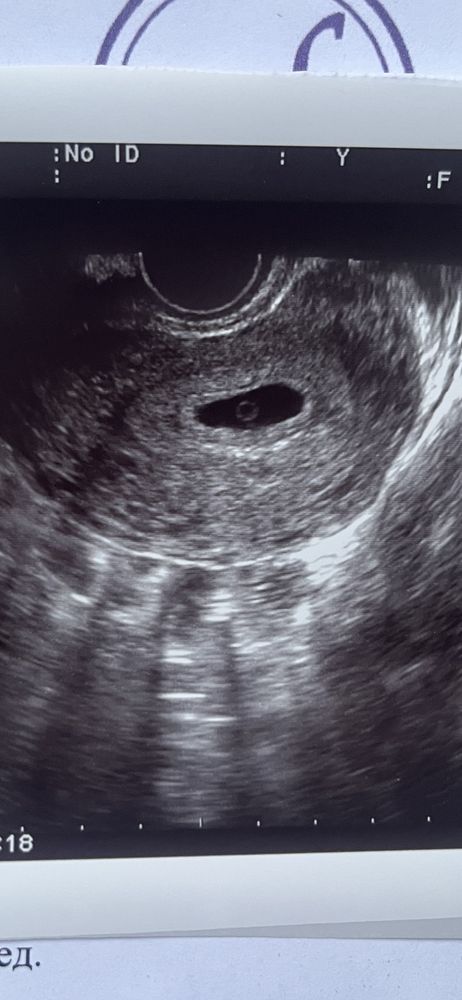

6 недель…опять пусто

Если есть жм, значит, есть и эмбрион овуляция возможно была позже, подождите еще 5-7 дней тоже вижу под жм что-то

Там желточный мешочек в центре, и ощущение, что рядом с ЖМ есть еще кое-то. Но даже если просто ЖМ, то еще неделя есть точно, чтобы эмбрион появился

Есть такое ощущение что что то виднеется под желточным мешочком🤷🏻‍♀️ Наверное уже просто хочется видеть (